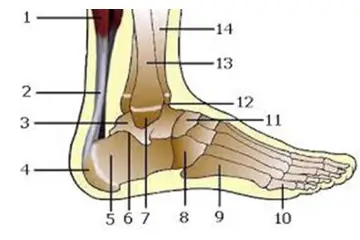

Ayak parmak kemik çıkıntısı, tıbbi literatürde "bunion" olarak adlandırılan, ayak başparmağının tabanında meydana gelen bir deformitedir. Bu durum, başparmağın yan tarafındaki kemikte bir çıkıntı oluşmasına neden olur ve genellikle ağrı, iltihaplanma ve hareket kısıtlılığı ile kendini gösterir. Bu makalede, ayak parmak kemik çıkıntısının belirtileri, nedenleri ve tedavi yöntemleri hakkında kapsamlı bilgiler sunulacaktır. Belirtiler Ayak parmak kemik çıkıntısının başlıca belirtileri şunlardır:

Nedenleri Ayak parmak kemik çıkıntısının oluşumuna katkıda bulunan çeşitli nedenler bulunmaktadır. Bunlar arasında: